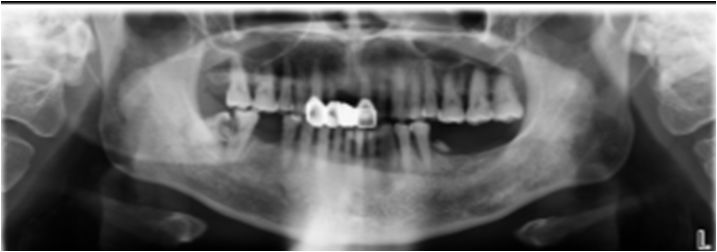

05 颌下间隙、颏下间隙

女,68岁,10天前自觉右侧下颌后牙区间断性钝痛,6天前发现右侧颌下区及颏下区肿胀,伴明显触压痛。

龋齿并冠周炎,咽旁间隙有肿大淋巴结。